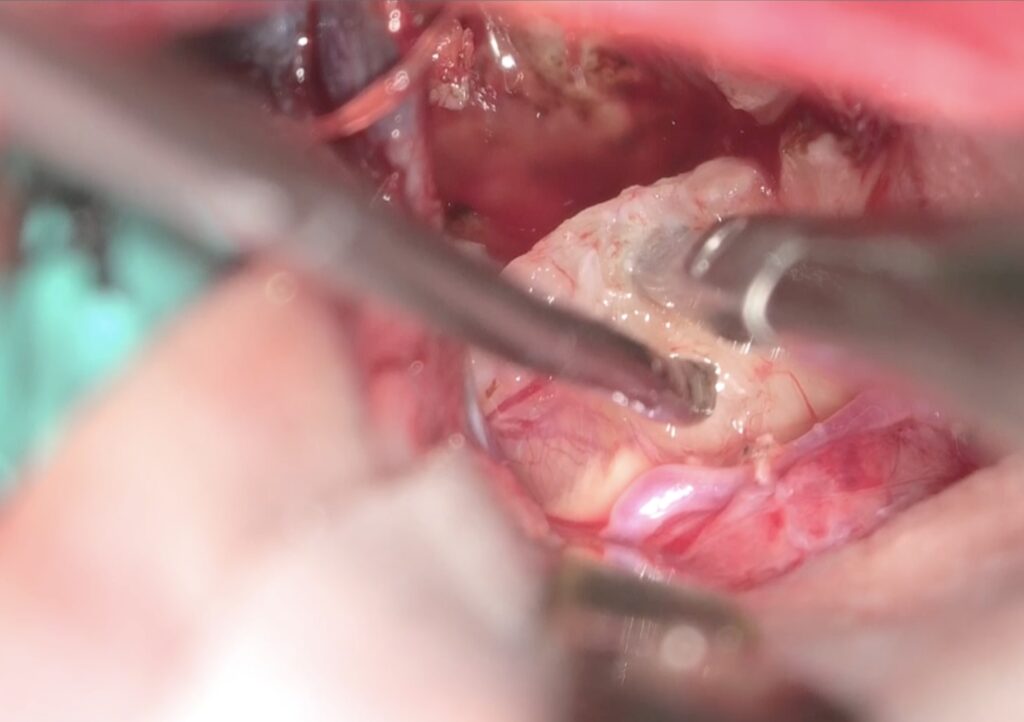

手術は通常通り行われ、顔面神経の麻痺を起こさずに摘出は終了し、うまくいったと考えていました。しかし術後より覚醒障害が続き、強い小脳腫脹を生じたため、術後脳室ドレナージ術、バルビタール麻酔療法、気管切開まで行い急性期を乗り切りました。術前より下肢静脈血栓症を合併していたことと、Petrosal veinが通常より広範囲の静脈環流を行っていたためと考えられます。現在、覚醒し、四肢が動くようになってきました。

手術は通常通り行われ、顔面神経の麻痺を起こさずに摘出は終了し、うまくいったと考えていました。しかし術後より覚醒障害が続き、強い小脳腫脹を生じたため、術後脳室ドレナージ術、バルビタール麻酔療法、気管切開まで行い急性期を乗り切りました。術前より下肢静脈血栓症を合併していたことと、Petrosal veinが通常より広範囲の静脈環流を行っていたためと考えられます。現在、覚醒し、四肢が動くようになってきました。